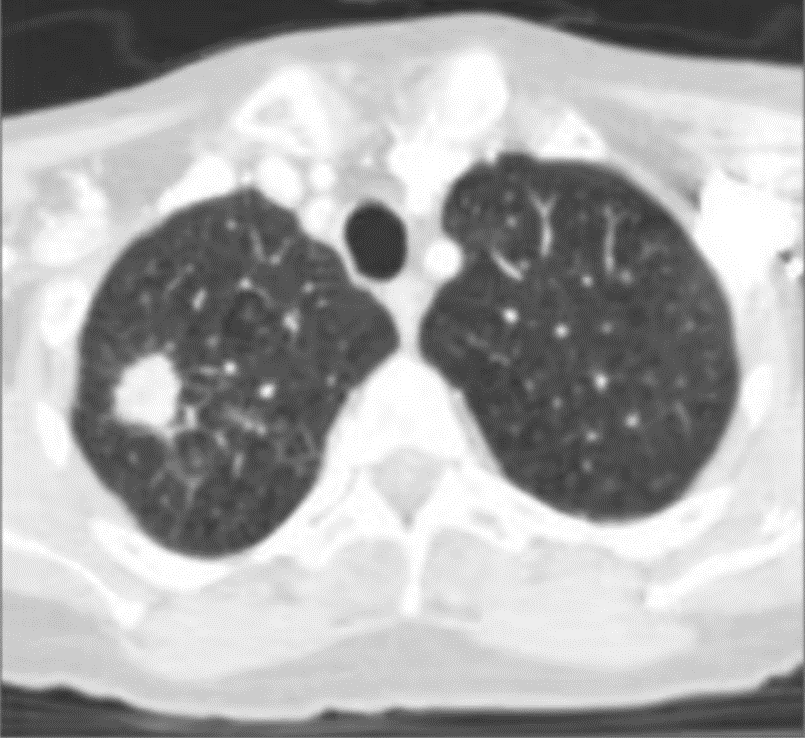

The patient had a history of smoking and chronic obstructive pulmonary disease (COPD). She was initially diagnosed with a right upper lobe (RUL) lung lesion, which was PET-positive. Four years ago, the lesion measured 1 cm in diameter and showed no metabolic activity, so no intervention was performed at that time.

However, she later developed severe shortness of breath and coughing. A repeat chest CT revealed that the lesion had enlarged to 1.5 × 1.2 cm. A biopsy confirmed non–small cell lung cancer, and she was diagnosed with Stage IA NSCLC (T1N0M0).

CyberKnife Treatment Plan Parameters

- Tumor volume: 3.6 cm³

- Prescription dose: 54 Gy / 3 fractions

- Target coverage: 100%

- Tracking system: Xsight Lung Synchrony (no fiducial markers required)

- Algorithm: Monte Carlo algorithm

- Collimator size:*20–30 mm

- Number of beams: 148

- Prescription isodose line: 75%